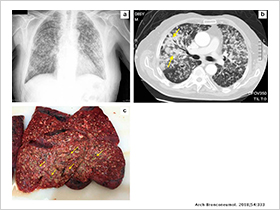

Recently, the Chilean Journal of Infectology published a scientific article with a comparative analysis between our Galactomannan kit (Vircell) and that of …